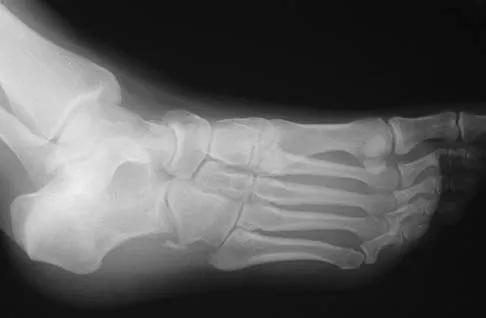

A 28-year-old professional dancer reports a 3-month history of progressive pain in the posterior aspect of the left ankle. Her symptoms are worse when she assumes the en pointe position. Examination reveals tenderness to palpation at the posterolateral aspect of the ankle posterior to the peroneal tendons which is made worse with passive plantar flexion. There is no nodularity, fluctuance, or tenderness of the Achilles tendon. The neurovascular examination is unremarkable. A lateral radiograph and MRI scan are shown in Figures 16a and 16b, respectively. Management should consist of

Explanation

The imaging studies reveal findings typical of the os trigonum syndrome. This condition results from inflammation between the os trigonum and the adjacent talus. The symptoms of posterior ankle pain are exacerbated by plantar flexion, which stresses the fibrous union between these two bones. Definitive management of the high-level athlete involves excision of the os trigonum from a medial approach, although arthroscopic excision has also been described. The os trigonum is not an intra-articular structure; therefore, ankle arthroscopy is neither diagnostic nor therapeutic. Abramowitz Y, Wollstein R, Barzilay Y, et al: Outcome of resection of a symptomatic os trigonum. J Bone Joint Surg Am 2003;85:1051-1057. Mouhsine E, Crevoisier X, Leyvraz P, et al: Post-traumatic overload or acute syndrome of the os trigonum: A possible cause of posterior ankle impingement. Knee Surg Sports Traumatol Arthrosc 2004;12:250-253.